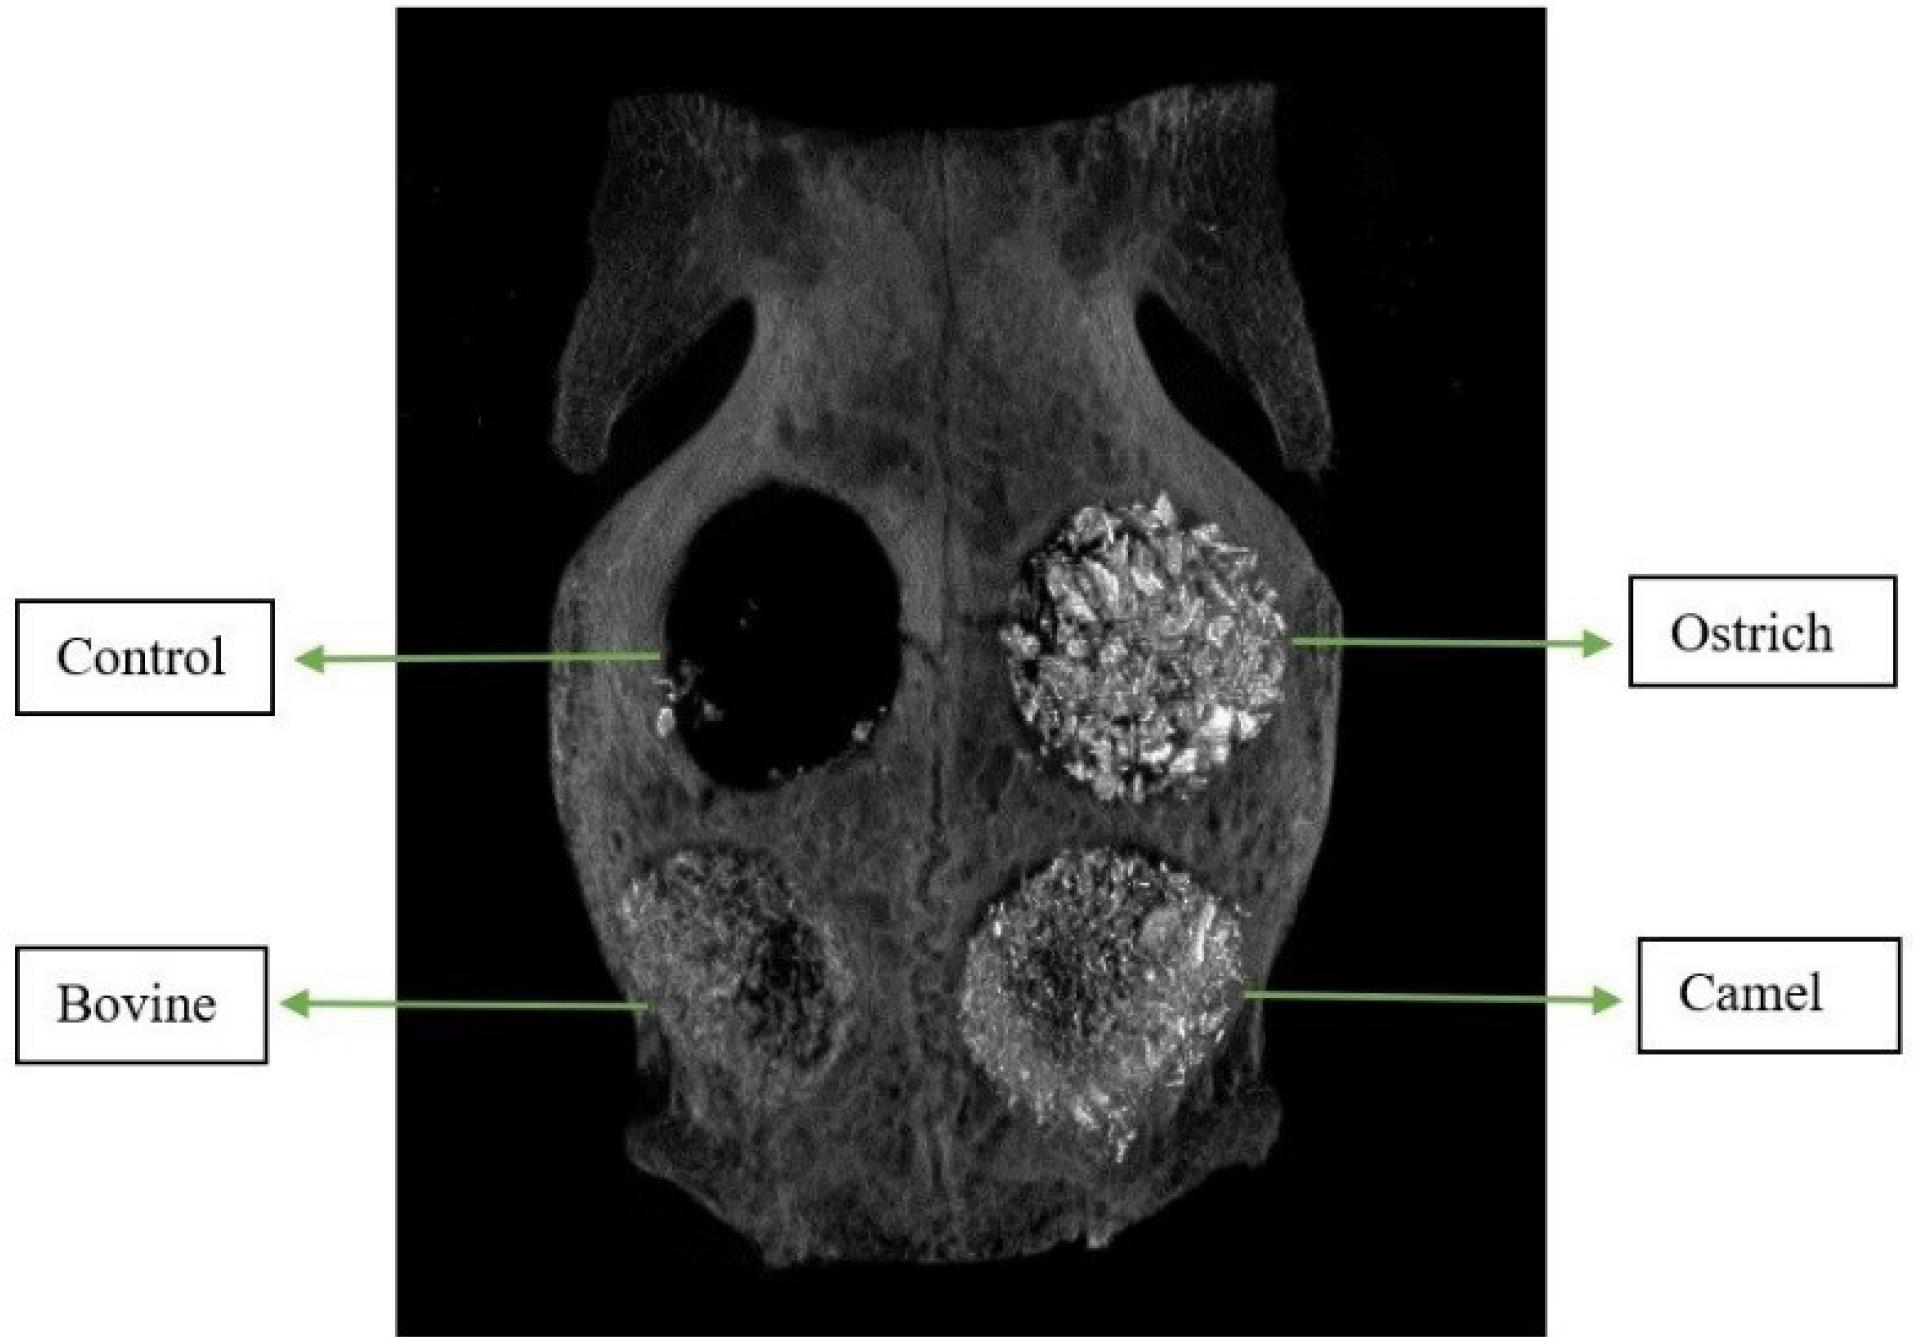

Figure 5 shows the means of BV/TV. The highest BV/TV was observed in DCB groups after 8 and 12 weeks, while the lowest amount belonged to the control groups. For both 8-week and 12-week groups, control groups showed significant differences from the other three groups (P < 0.001). Figure 6 shows an example of a micro-CT image.

Figure 6.

Sample of Micro-CT image of rabbit calvaria filled with three xenografts